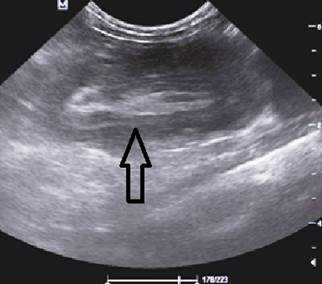

На рисунках 2 и 3 отображена ультразвуковая картина кишечной инвагинации.

Рис. 2. Симптом «мишени»

Ребёнку назначили УЗИ органов брюшной полости, которое выявило образование в виде двух тёмных (гипоэхогенных) колец со светлым (гиперэхогенным) кольцом между ними, напоминающее мишень.

В момент УЗ-исследования врач может определить один из симптомов:

- симптом мишени (за счёт внедрения одной кишки в другую инвагинат на срезе выглядит как мишень);